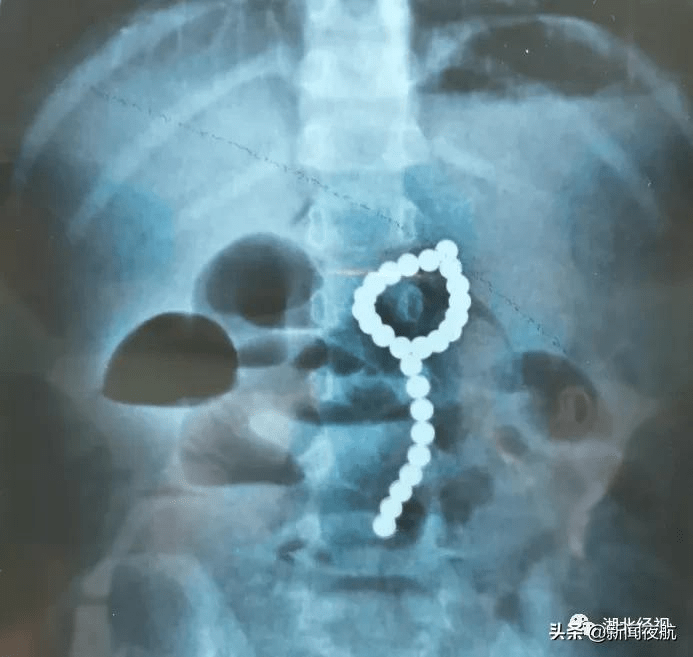

8月11日晚上 , 湖北鄂南的4岁女孩莎莎(化名)吃晚饭后总说“肚子痛” , 疼得厉害时大汗淋漓 , 还吐了几次 。 家长担心是吃坏了肚子 , 就带莎莎到当地医院就诊 。

拍片发现 , 莎莎腹部有异常高密度阴影 , 看形状像是一颗一颗的小珠子 , 一数有26颗 。

在父母的追问下 , 莎莎才说她吞了“彩色的小珠珠” , 推测应该是家里的玩具磁力珠 。 当地医生建议立即转院 , 12日清晨 , 莎莎一家到达武汉儿童医院 。

经过紧急术前检查 , 早上8点 , 医生给莎莎做了全麻下胃镜检查术 。 术中 , 医生发现莎莎胃里有大量成串的磁力珠 , 部分堆积在胃幽门口 , 成串的“骑跨”在胃角上 。

医生拨动磁力珠发现 , 有一颗磁力珠深陷在胃壁中 , 考虑穿孔可能很大 , 经讨论后 , 决定直接转外科手术 。

紧急与家长沟通并取得其同意后 , 医生对莎莎进行剖腹探查 , 结果在莎莎胃内探查到大量的磁力珠 , 在胃大弯、小弯处发现穿孔 , 证实了之前的推测 。 医生在胃内共找到26颗磁力珠并顺利取出 。